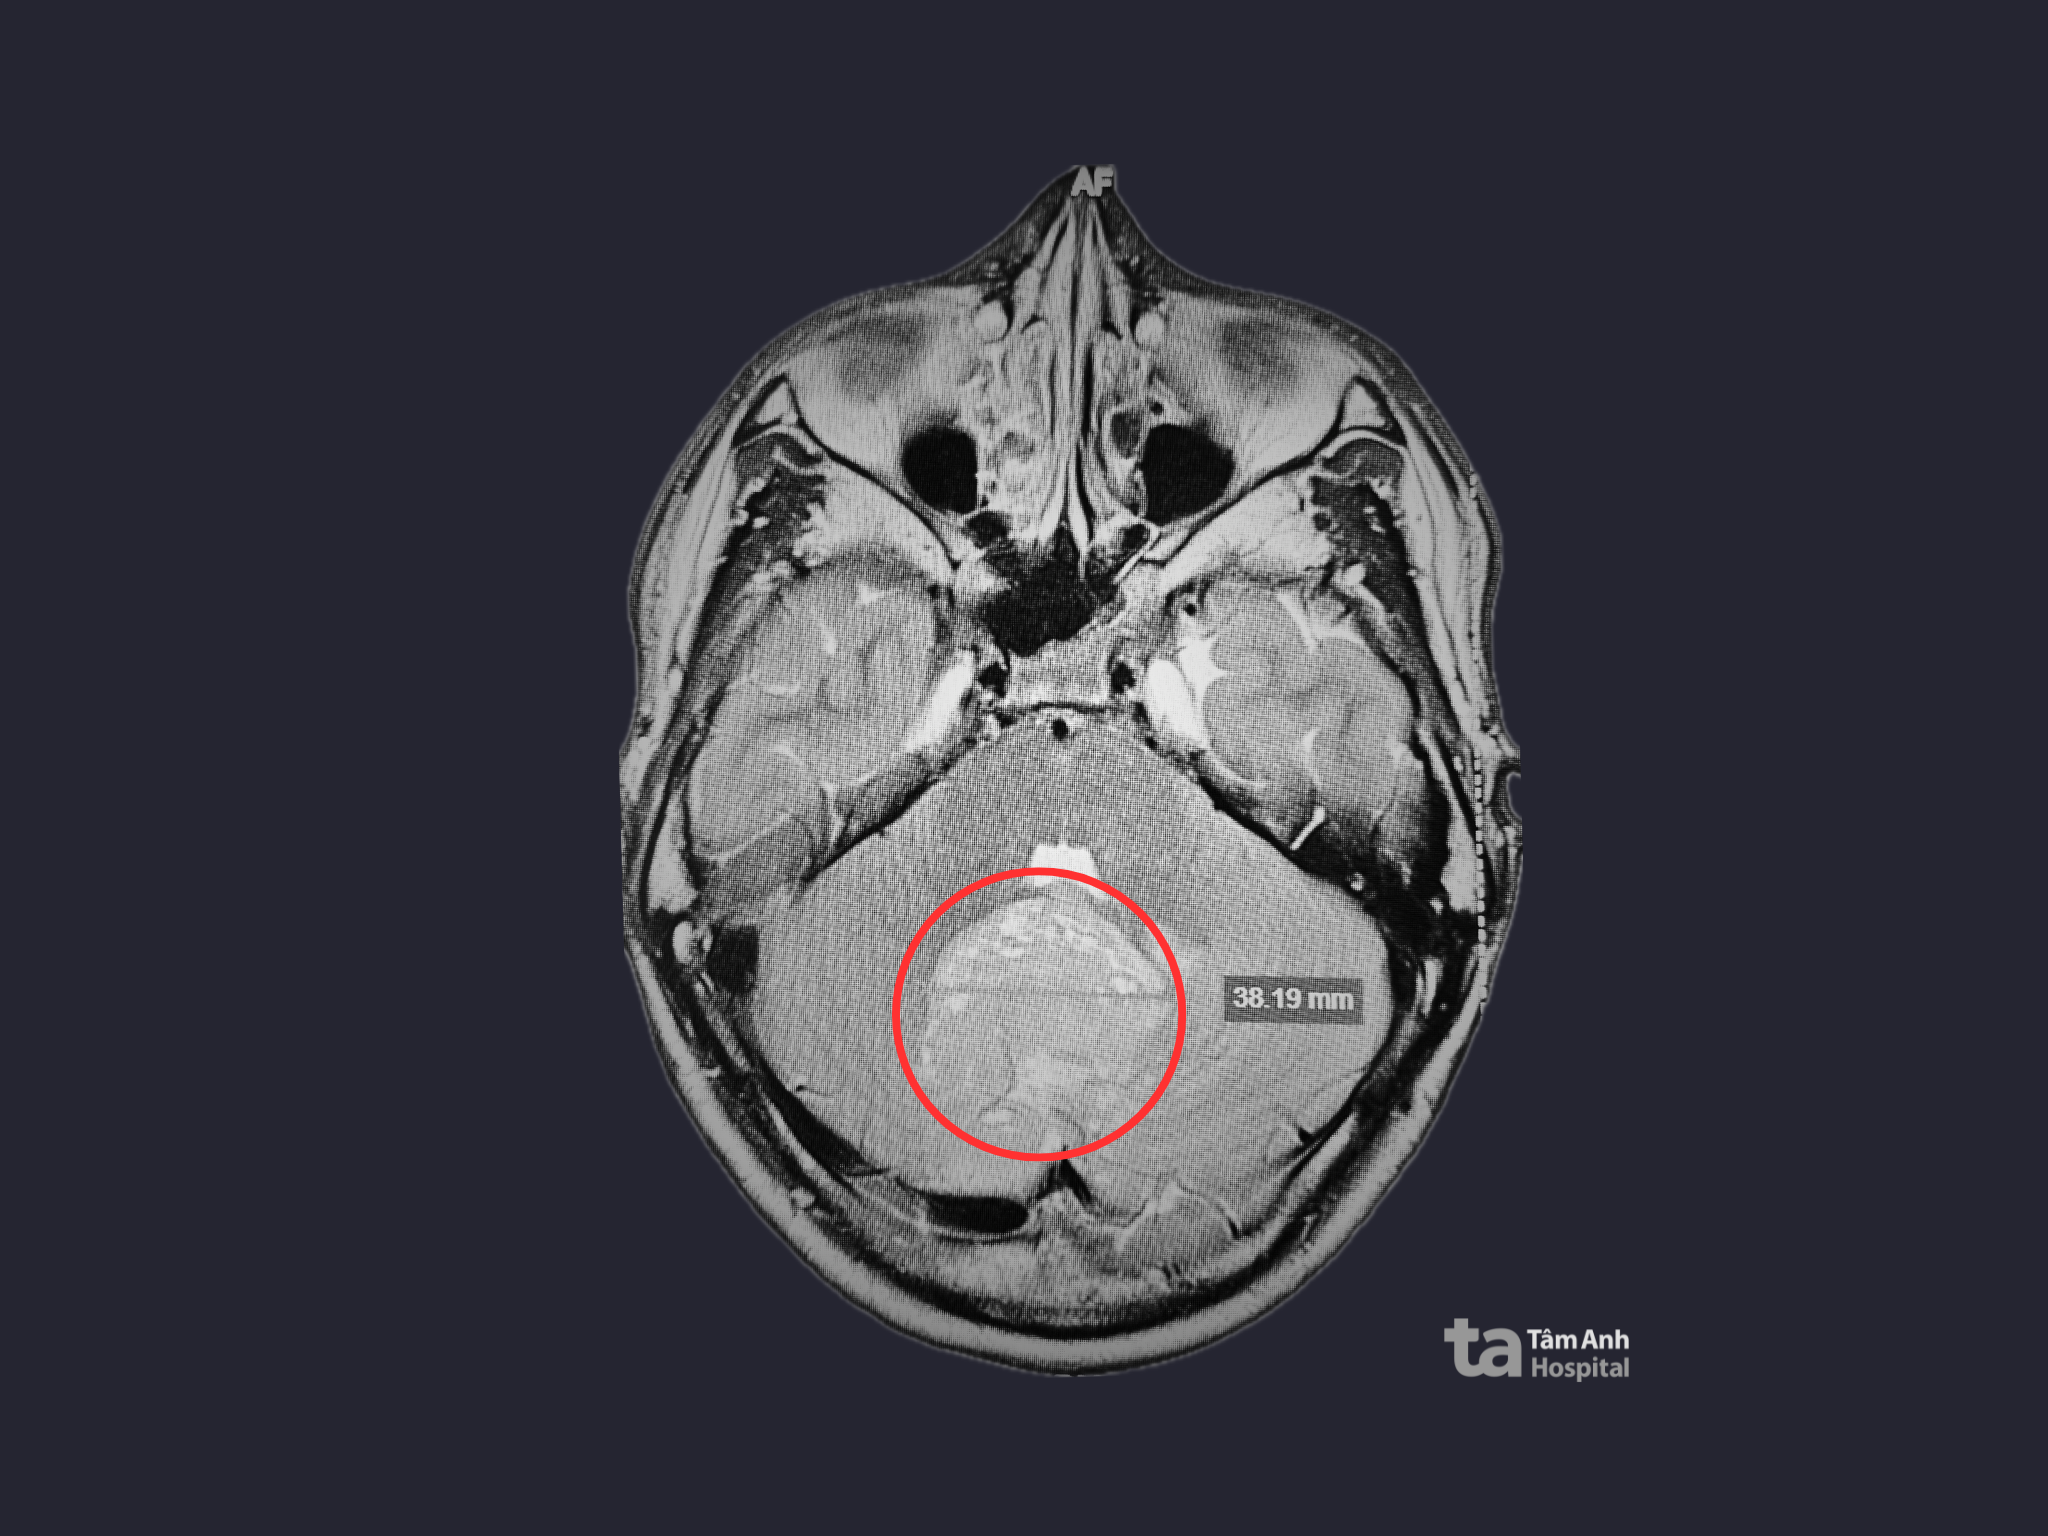

Thanh, an American exchange student home in Vietnam for summer break, began experiencing frequent, severe headaches accompanied by dizziness, blurred vision, and loss of balance. Attributing his symptoms to the change in weather and jet lag, Thanh initially delayed seeking medical attention. However, when his symptoms worsened, he went to Tam Anh General Hospital in Ho Chi Minh City for an examination. A 3 Tesla MRI scan of his brain revealed a large, 4.6 cm tumor in the vermis of the cerebellum. The tumor was compressing the 4th ventricle and cerebral aqueduct, causing dilation of the lateral and 3rd ventricles, periventricular edema, and tonsillar herniation through the foramen magnum.

A 3 Tesla MRI scan revealed the tumor located in Thanh's cerebellum. Photo: Tam Anh General Hospital